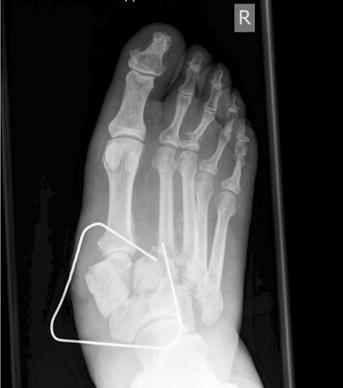

Zur topographischen, rein radiologischen Einteilung nach Befallsmuster wird meist die Klassifikation nach Sanders u. Frykberg verwendet. In Anlehnung an die Unterteilung von Sanders wird die diabetisch-neuropathische Osteoarthropathie in fünf Haupttypen klassifiziert, die den Hauptprädilektionsstellen der Erkrankung am Fuße entsprechen. Dabei wird die Häufigkeit für den Befall von Sanders & Frykberg wie folgt angegeben: Typ I = 15 % ‚Typ II = 40 % , Typ III = 30 % , Typ IV = 10 % und Typ V = 5 %. Koller ermittelte ähnliche Ergebnisse in seiner Studie 20. Die häufigsten Veränderungen am Fuß der diabetisch-neuropathischen Osteoarthropathie entfallen somit auf die Typen I, II und III (ca. 80 %). Nicht selten zeigt sich ein kombiniertes Befallsmuster (Abb. 2) 21.

- Typ I: Beim Typ I findet man Knochennekrosen im Bereich der Metatarsophalangealgelenke. Diese Nekrosen können zur sogenannten „candy stick deformity“ („Zuckerstängel-Deformität“) des Knochens führen, mit der Gefahr der knöchernen Durchspießung der Fußsohlenhaut.

- Typ II: Typ II betrifft die Tarsometatarsalgelenke, also den Bereich des Lisfranc-Gelenks, und hat als wesentliche Konsequenz – wie beim Typ III – den Verlust der Rückfußstatik zur Folge. Es kommt häufig zur Ausbildung eines Knick-Plattfußes mit deutlicher Vorfußabduktion.